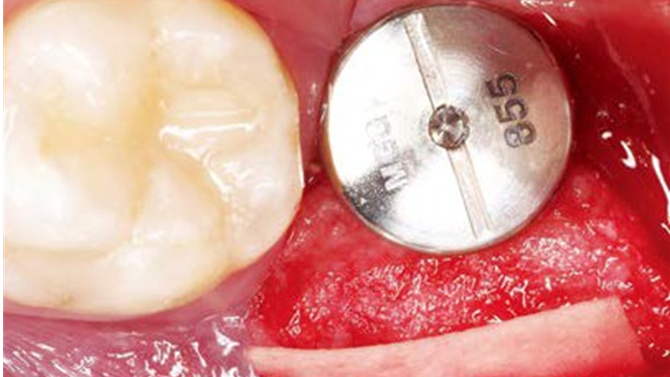

Clinical case: Bone filling into the bottom of deepest thread at 8.0mm AnyRidge fixture

- Courtesy of Dr. Kwang Bum Park -

AnyRidge, Knifethread ,extraction socket, ,initial stability ,Allograft, ,osseointegratio ,Dr. Kwang Bum Park, , Mandibular, Single replacement, AnyRidge, Mega-oss,

Implant system-AnyRidge, Regeneration-Mega-Oss

Thanks to MegaGen’s unique KnifeThread® and super self-tapping design, better initial stability can be attained in any compromised bone situation.

The design enables bone condensing, gentle ridge expansion, maximized compressive force resistance, and minimized shear force production.